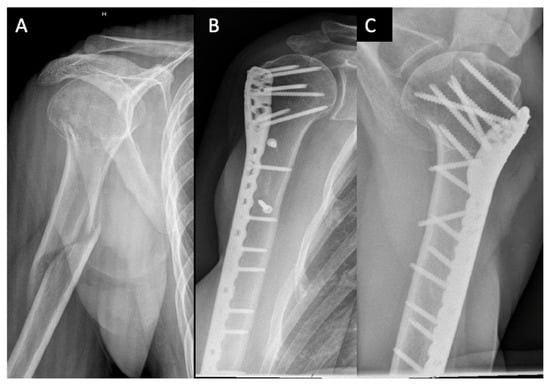

| Case | Age, years | Sex | Neer | AO/OTA Proximal | AO/OTA Metaphyseal | Stedtfeld | Garnavos/ Lasanianos | Implant/ Metaphyseal Fixation | FU, Months/ CMS-K | Revision |

|---|---|---|---|---|---|---|---|---|---|---|

| 1 | 65 | M | IV | 11-B1 | 12-C2 | D4 | Combined | Retrograde nail | 48/83 | - |

| 2 | 74 | F | III | 11-A3 | 12-C3 | A2 | Extended | T-nail | 97/51 | Metaphyseal lack of fixation, material removal |

| 3 | 68 | F | IV | 11-B1 | 12-C1 | D2 | Extended | T-nail | 32/71 | Metaphyseal lack of fixation, change to plate |

| 4 | 43 | M | IV | 11-B1 | 12-C3 | D3 | Extended | T-nail/cerclage | 92/77 | - |

| 5 | 74 | F | V | 11-B2 | 12-C1 | B1-3 | Extended | T-nail/screw | 52/64 | - |

| 6 | 65 | M | III | 11-A2 | 12-A1 | A2 | Extended | T-nail/screw | 60/62 | - |

| 7 | 75 | F | III | 11-A2 | 12-C1 | C3 | Extended | T-nail | 91/64 | - |

| 8 | 72 | F | VI | 11-C3 | 12-C3 | D3 | Extended | T-nail/screw | 55/68 | Metaphyseal lack of fixation, inverse prothesis |

| 9 | 55 | F | III | 11-A2 | 12-C1 | B2-1 | Extended | T-nail | 70/99 | - |

| 10 | 67 | F | III | 11-A2 | 12-C1 | C2 | Extended | Locking plate/ cerclage, lag screw | 63/99 | - |

| 11 | 37 | F | IV | 11-B1 | 12-C1 | D3 | Extended | T-nail/screw | 34/86 | - |

| 12 | 50 | F | III | 11-A2 | 12-C1 | C4 | Combined | T-nail/cerclage | 49/97 | - |

| 13 | 76 | F | V | 11-C2 | 12-C2 | D4 | Combined | Locking plate/ lag screw | 58/65 | - |

| 14 | 71 | M | IV | 11-B1 | 12-C1 | D4 | Extended | T-nail/screw | 15/38 | Loss of reduction, proximal nail displacement, material removal |

| 15 | 70 | F | IV | 11-B1 | 12-C2 | D4 | Combined | T-nail/cerclage | 15/70 | - |

| 16 | 23 | M | IV | 11-B2 | 12-C2 | D4 | Combined | Locking plate/ plate | 35/99 | - |

| 17 | 46 | F | V | 11-C2 | 12-C3 | B1-3 | Extended | Locking plate/ lag screw | 57/100 | - |

| 18 | 76 | F | III | 11-A2 | 12-C1 | C2 | Extended | T-nail | 12/72 | - |

| 19 | 53 | F | III | 11-A3 | 12-C3 | C3 | Extended | T-nail/screw | 12/48 | Metaphyseal lack of fixation, change to plate |

| 20 | 53 | F | IV | 11-B1 | 12-A1 | B2-3 | Extended | T-nail | 12/74 | - |

| 21 | 51 | F | IV | 11-B1 | 12-C1 | D2 | Extended | Locking plate/ lag screw | 37/89 | - |

| 22 | 49 | M | V | 11-C2 | 12-C3 | D2 | Combined | Locking plate/ plate | 61/50 | - |

| 23 | 48 | F | V | 11-C2 | 12-C3 | B1-3 | Extended | Locking plate | 45/84 | - |

| 24 | 68 | M | IV | 11-B1 | 12-C1 | B1-2 | Extended | Locking plate/ lag screw | 12/45 | Metaphyseal lack of fixation, pseudarthrosis |

| 25 | 74 | F | III | 11-C1 | 12-C3 | C3 | Extended | Locking plate/ cerclage | 13/62 | - |

| Characteristics | Nail (n = 16) | Plate (n = 9) | p-Value |

|---|---|---|---|

| Age, years | 62.6 ± 12.4 | 55.8 ± 17.0 | 0.33 |

| Sex | 12F, 4M | 6F, 3M | 0.76 |

| High-energy trauma | n = 6, 37.5% | n = 3, 33.3% | – |

| ASA | 2.1 ± 0.7 | 2.2 ± 0.4 | 0.85 |

| Follow-up, months | 46.6 ± 29.9 | 42.3 ± 19.7 | 0.98 |

| CMS-K | 70.3 ± 32.3 | 76.0 ± 31.0 | 0.42 |

| Postoperative revision | n = 5; 31.3% | n = 1; 11.1% | – |